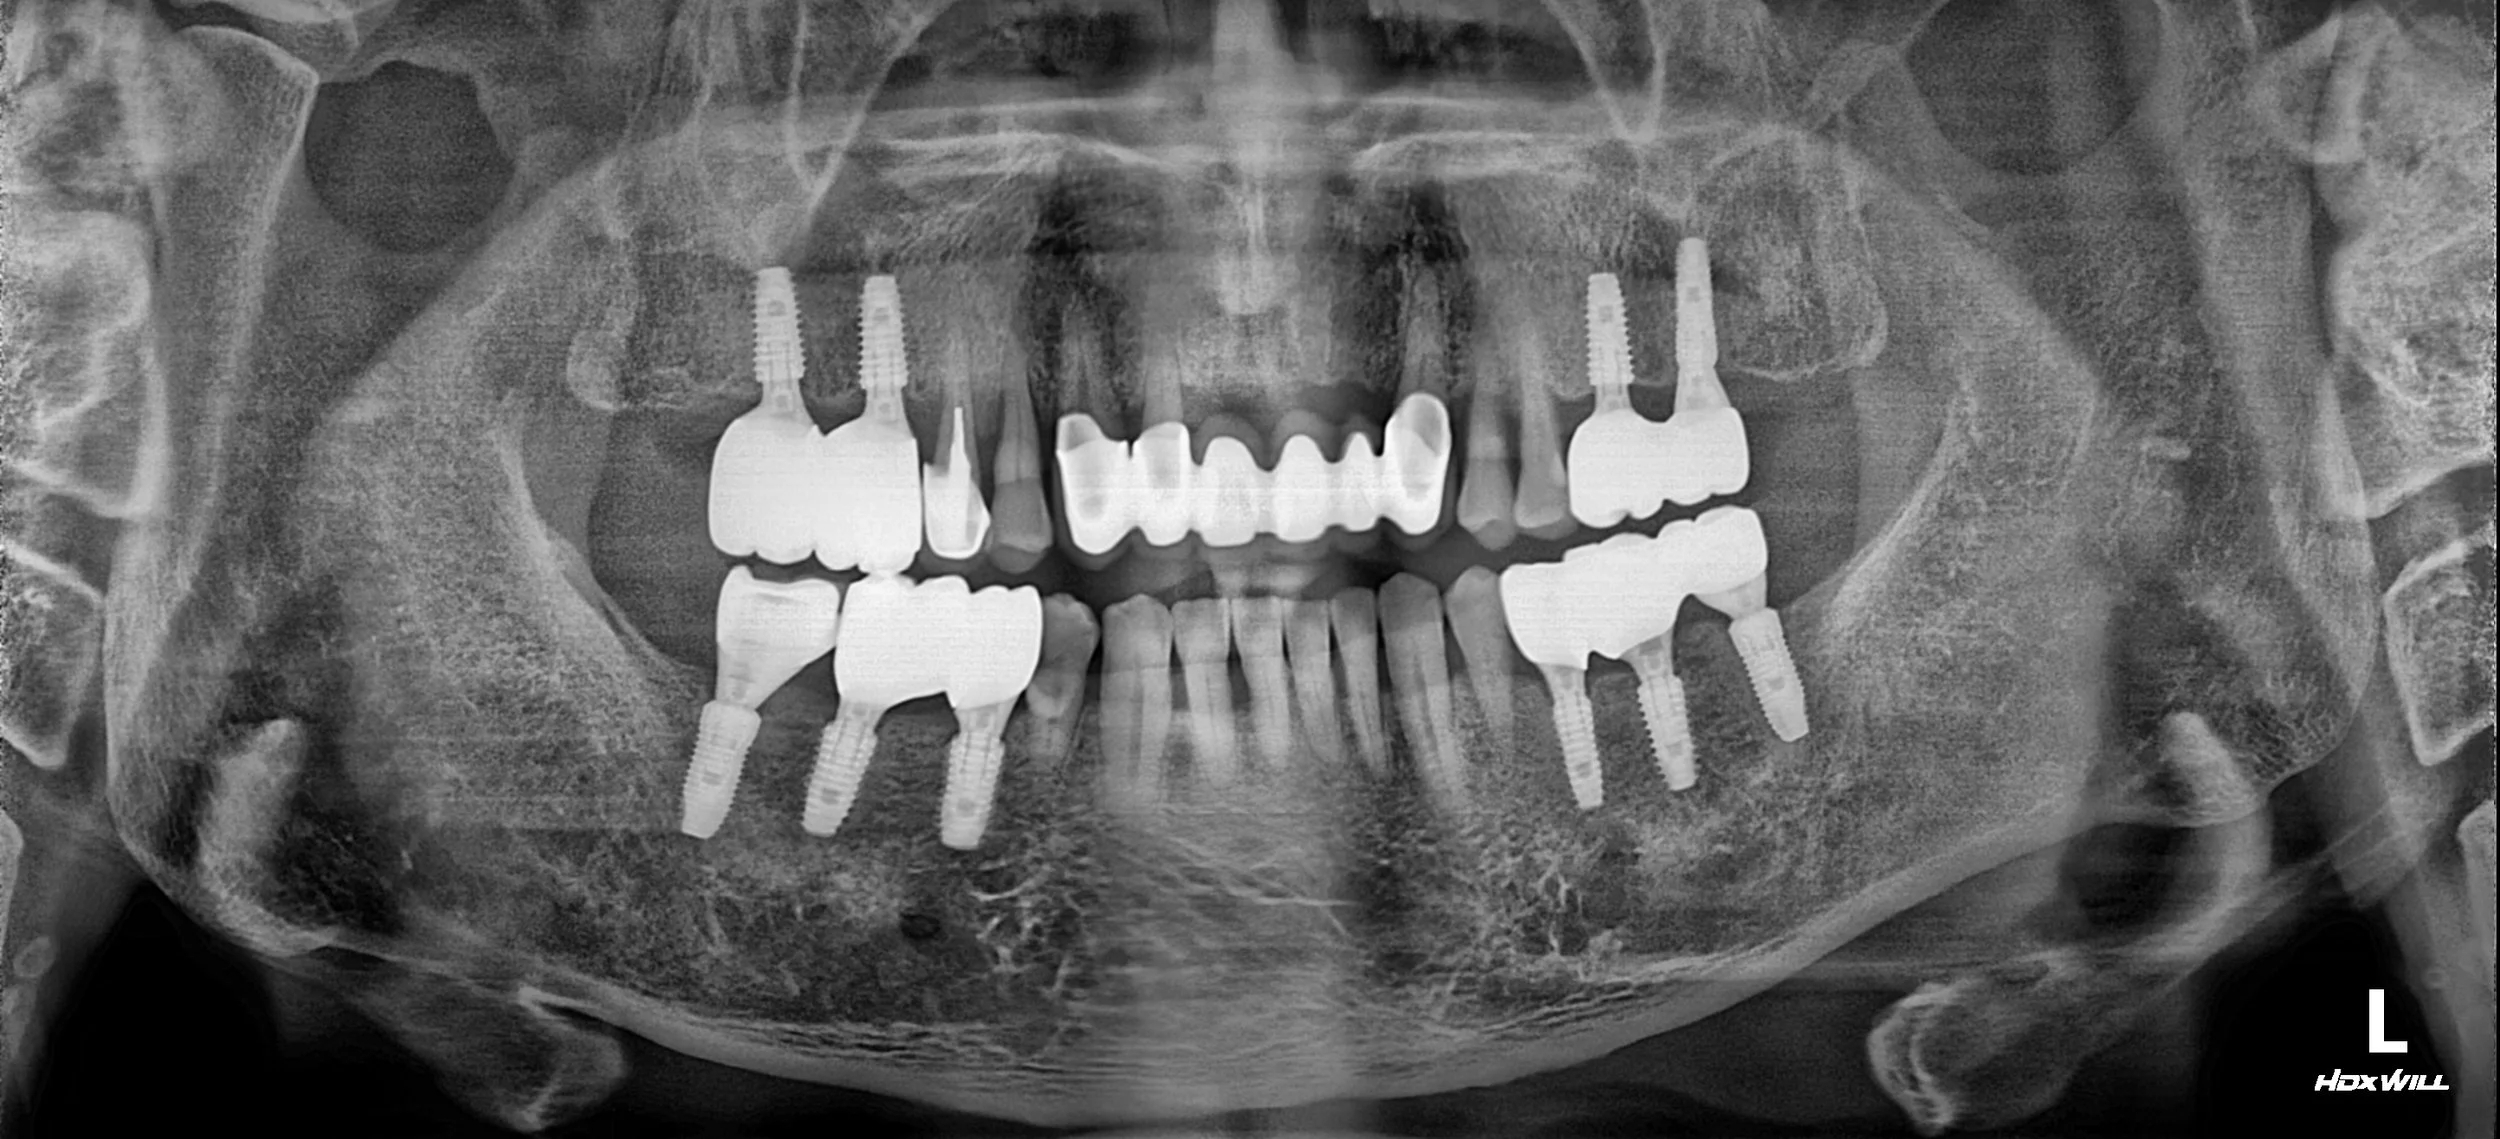

Treatment Approach

The treatment followed a meticulous sequence to ensure long-term sustainability:

1. Initial Stabilization: Comprehensive periodontal debridement was performed to control infection. Hopeless teeth were managed, and the foundation was secured.

2. Occlusal Height & Curve Establishment: Using the existing and newly placed implants, the Vertical Dimension (VDO) was stabilized. A particular focus was placed on creating an ideal occlusal curve to distribute forces evenly across the arches.

3. Adaptation Phase: The patient’s functional adaptation to the new occlusal scheme was monitored using long-term provisional restorations. This ensured the stability of the TMJ and neuromuscular system before finalization.

4. Definitive Restoration: Once the occlusion was stabilized, the final restorations were delivered. The anterior segment received ceramic bridges that were carefully contoured to harmonize with the patient’s facial features while maintaining functional integrity.

The result is a healthy, maintainable oral environment with a balanced occlusion and a significantly improved aesthetic profile.